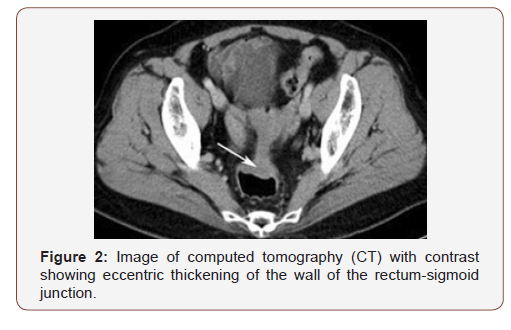

The diagnostic suspicion of intestinal endometriosis is mainly clinical, based on symptomatology; however, the lack of pathological signs makes diagnosis difficult; even during surgery intestinal endometriosis is confused with neoplasms, despite the use of computed tomography (CT) tomography [1,14], Figure 2 or magnetic resonance imaging (MRI), lto detection of wall nodules within the attached masses, when the atypical characteristics in the MRI sequences suggest a possible malignant Figure 3. It is generally diagnosed by histological findings after surgical resection [12] (Figures 4-6).